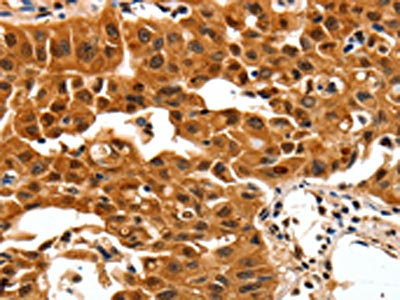

• The image on the left is immunohistochemistry of paraffin-embedded Human lung cancer tissue using CSB-PA179192(YWHAB Antibody) at dilution 1/30, on the right is treated with synthetic peptide. (Original magnification: ×200)

• The image on the left is immunohistochemistry of paraffin-embedded Human colon cancer tissue using CSB-PA179192(YWHAB Antibody) at dilution 1/30, on the right is treated with synthetic peptide. (Original magnification: ×200)